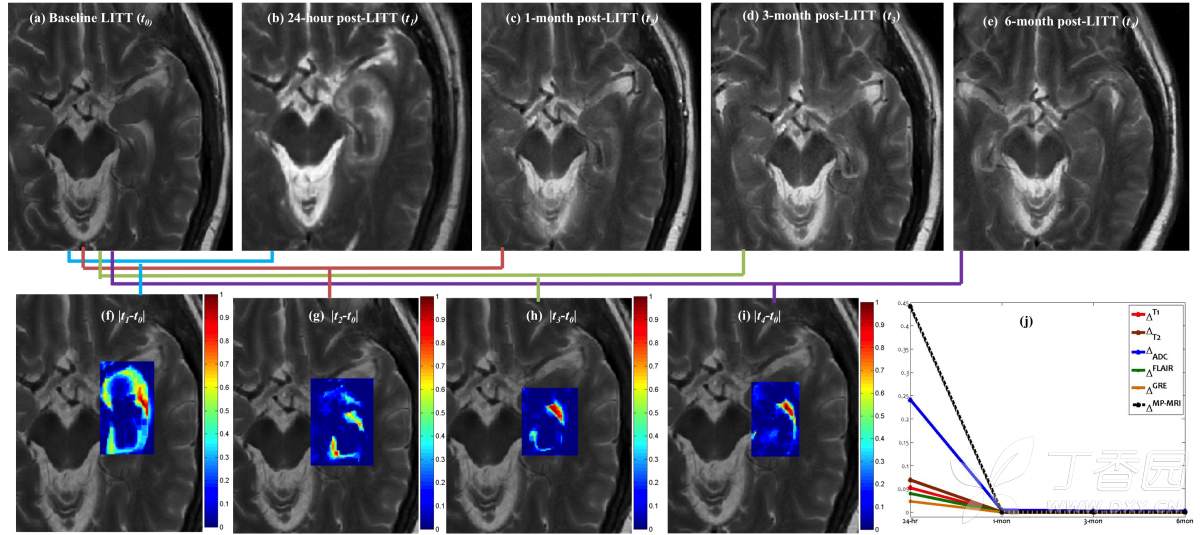

A:LITT技术可能会使病变周围产生水肿。从影像角度看,LITT术后血脑屏障破坏,随后出现新生血管逐渐修复;其他的发现包括外周强化和治疗肿瘤初始边界外的扩散受限。此外,对于一些病灶大的病变,LITT技术可能也不适用,可能出现组织体积增加和水肿效应等。

对于这些副作用如何有效规避?INC加拿大James Rutka教授指出,激光热消融后的病灶及周围水肿可能需要额外的药物或手术治疗,以避免神经功能恶化。目前也有一种有计划切除消融组织的方法可以减少水肿的进展,但这需要主治医师拥有丰富的LITT技术经验才能有效避免。